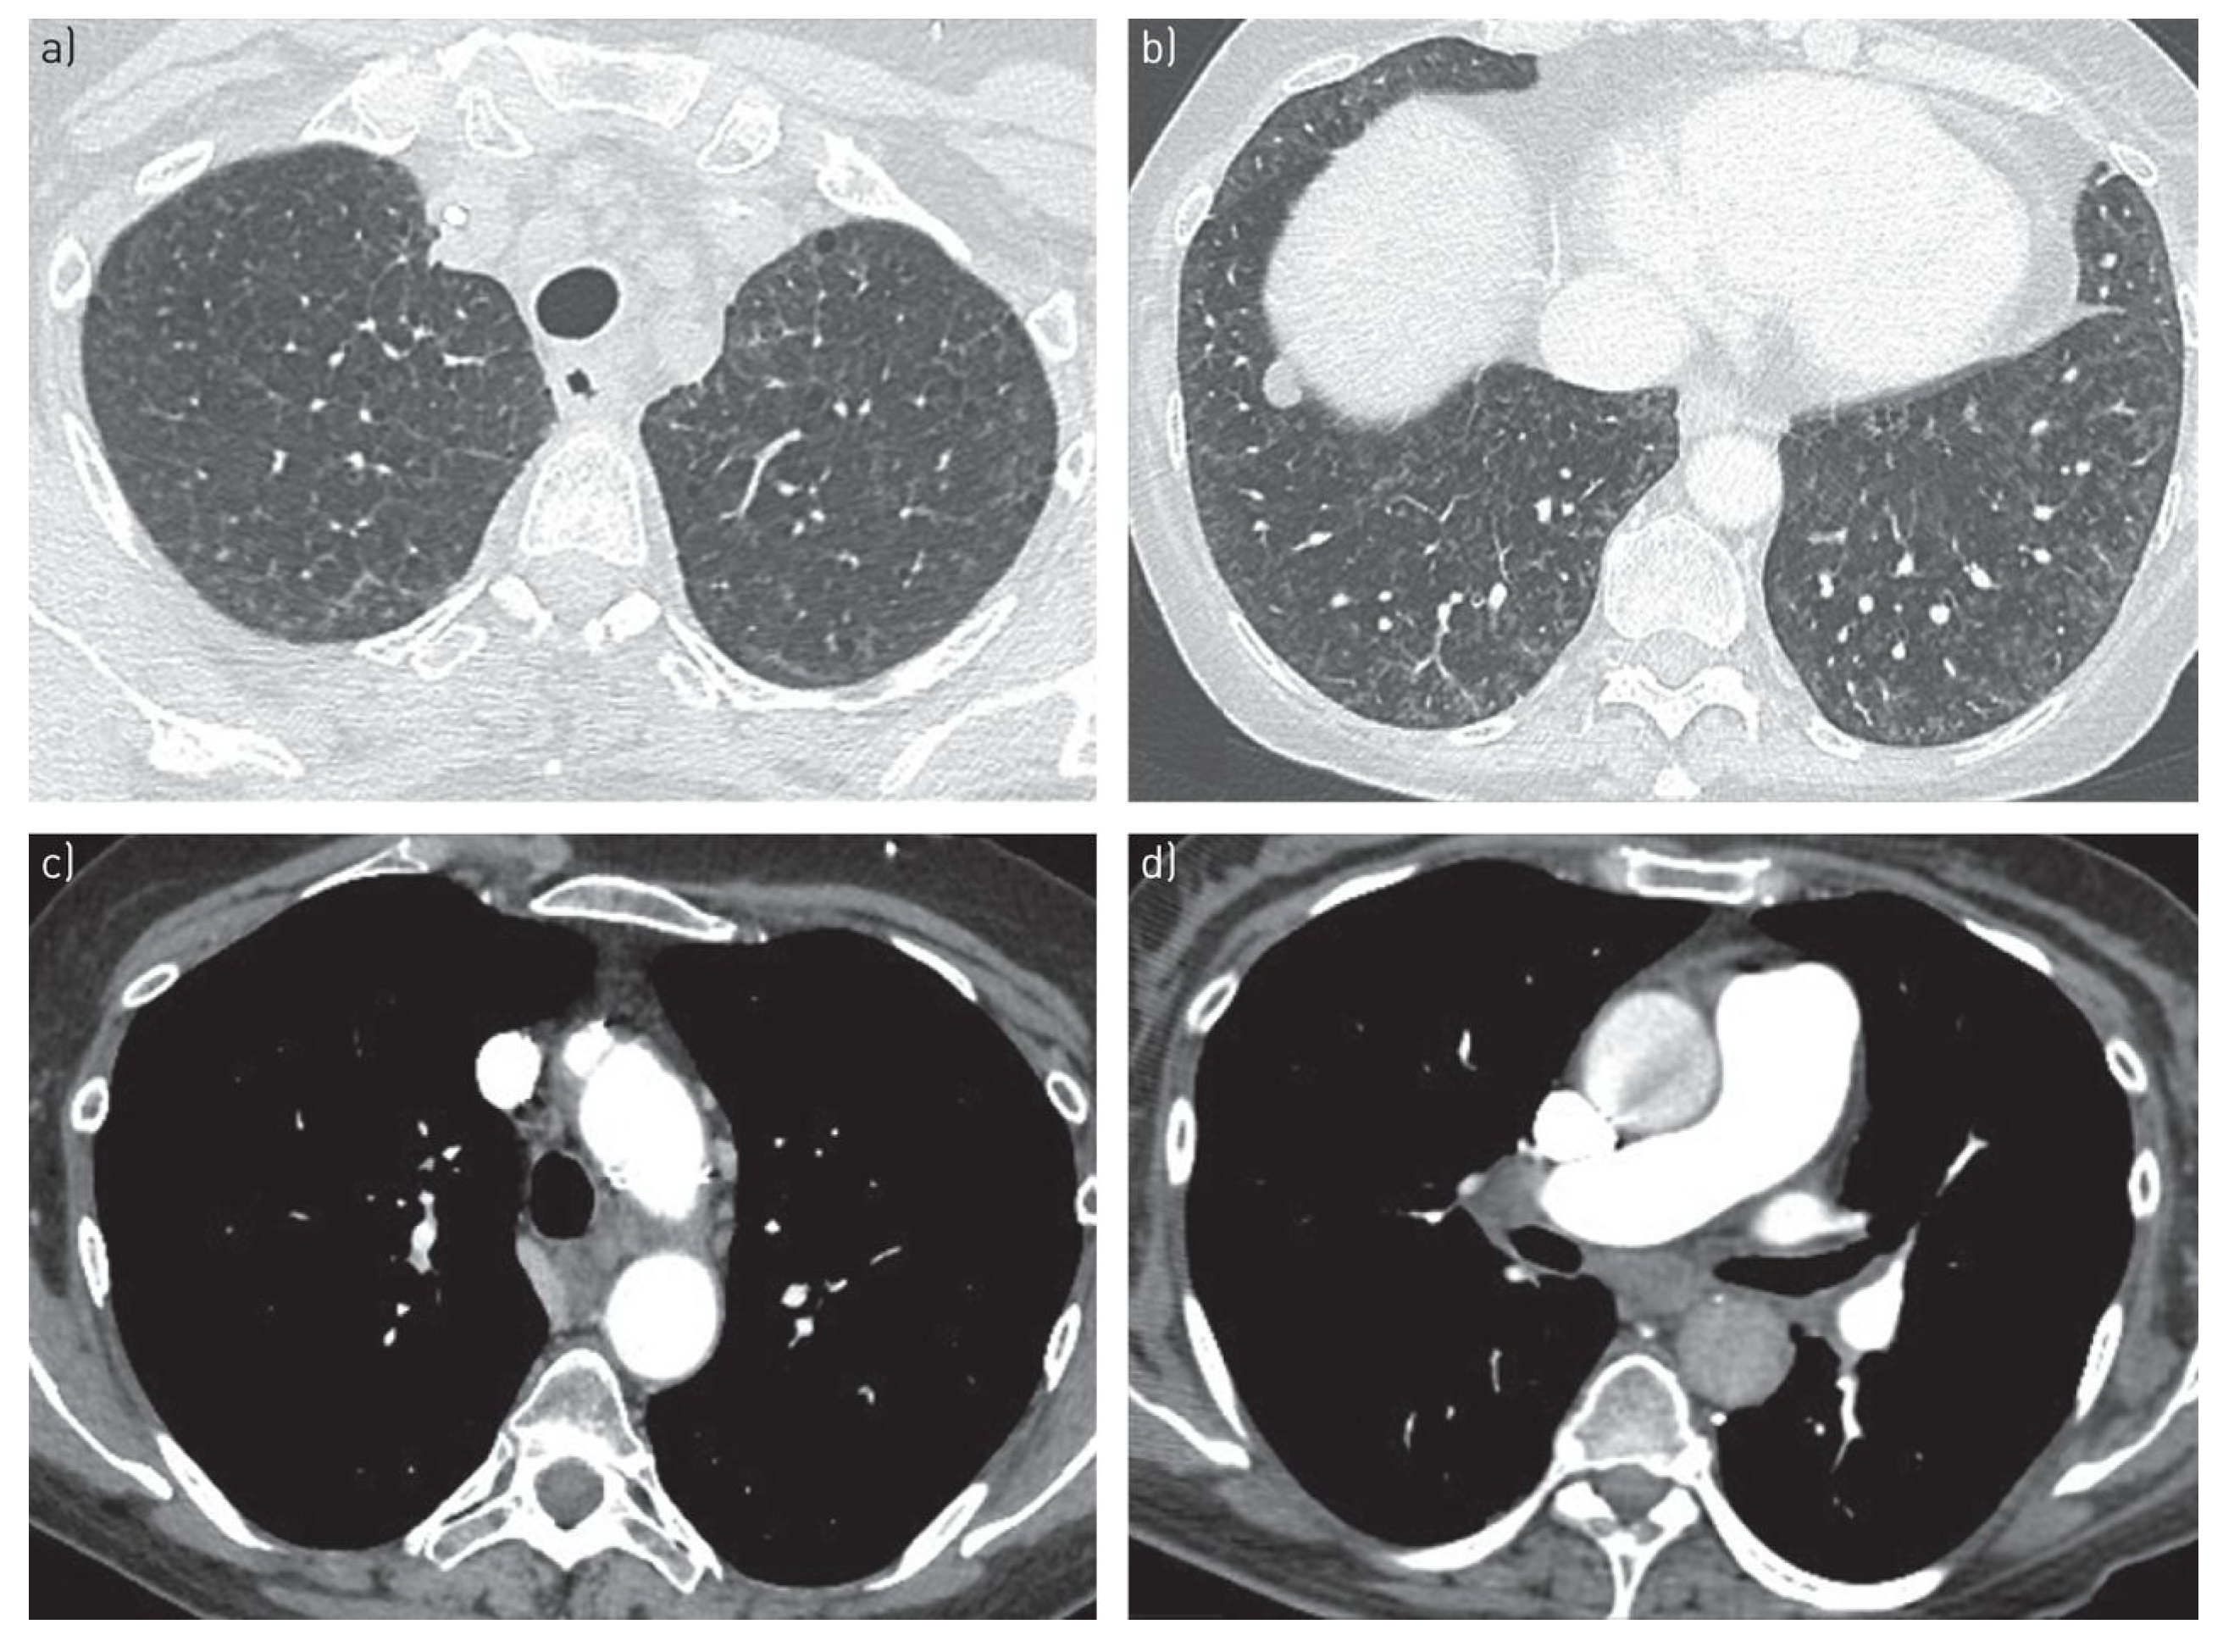

6.2. High-Resolution Computed Tomography (HRCT)

- Resten, A.; Maitre, S.; Humbert, M.; Rabiller, A.; Sitbon, O.; Capron, F.; Simonneau, G.; Musset, D. Pulmonary hypertension: CT of the chest in pulmonary venoocclusive disease. Am. J. Roentgenol. 2004, 183, 65–70. [Google Scholar] [CrossRef]

- Montani, D.; Achouh, L.; Dorfmüller, P.; Le Pavec, J.; Sztrymf, B.; Tchérakian, C.; Rabiller, A.; Haque, R.; Sitbon, O.; Jaïs, X.; et al. Pulmonary veno-occlusive disease: Clinical, functional, radiologic, and hemodynamic characteristics and outcome of 24 cases confirmed by histology. Medicine 2008, 87, 220–233. [Google Scholar] [CrossRef]

- Montani, D.; Lau, E.M.; Dorfmüller, P.; Girerd, B.; Jaïs, X.; Savale, L.; Perros, F.; Nossent, E.; Garcia, G.; Parent, F.; et al. Pulmonary veno-occlusive disease. Eur. Respir. J. 2016, 47, 1518–1534. [Google Scholar] [CrossRef]

- Ali, N.; Loughborough, W.W.; Rodrigues, J.C.L.; Suntharalingam, J.; Hudson, B.; Hall, T.; Augustine, D.; Mackenzie, R.; Robinson, G. Computed tomographic and clinical features of pulmonary veno-occlusive disease: Raising the radiologist’s awareness. Clin. Radiol. 2019, 74, 655–662. [Google Scholar] [CrossRef]

| HRCT findings | Classic triad: centrilobular ground-glass opacities, smooth interlobular septal thickening, mediastinal lymphadenopathy | Enlarged pulmonary arteries; otherwise often normal parenchyma |